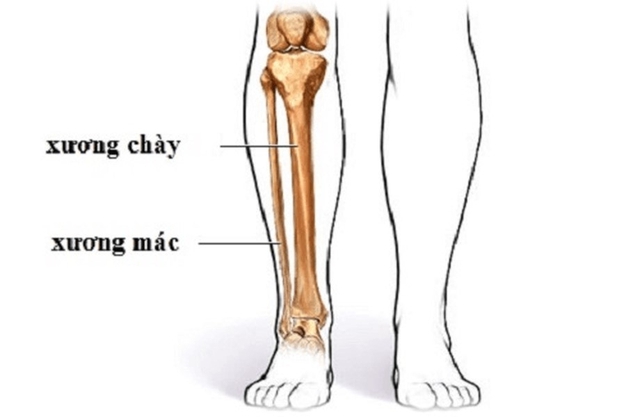

Cấu tạo cẳng chân (hình ảnh minh họa, nguồn: internet)